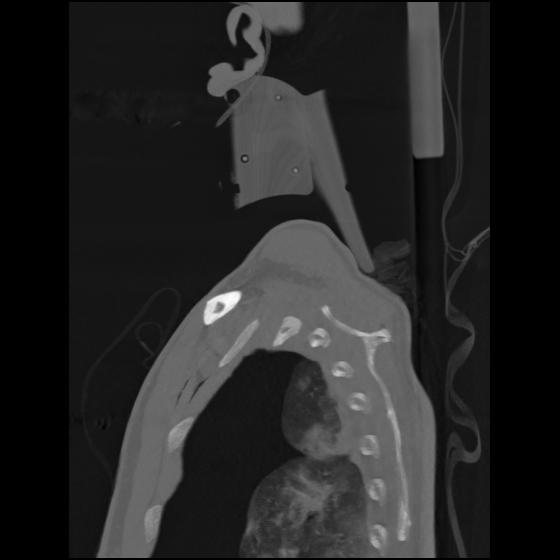

24 ANGIO,CE,Sag-MIP,5.000,ANGIO,Sag-MIP,